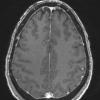

NEOPLASMS (GLIAL)

Astrocytoma, IDH-mutant, WHO Grade 2 (6)